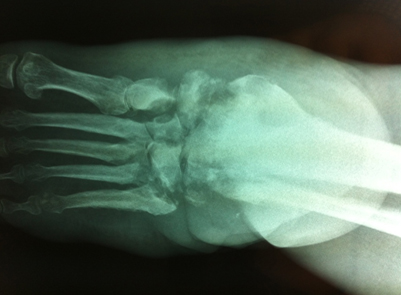

Une redoutable infection

Dr Jacques Fechtenbaum Hôpital Cochin - Paris

Mr B., 46 ans, présente un diabète insulinodépendant. Une neuropathie périphérique et une artériopathie débutante se sont installées. Il présente un mal perforant plantaire sous le pied gauche et un érysipèle de la jambe gauche.

Les douleurs sont très intenses, l’impotence fonctionnelle totale, le syndrome inflammatoire et infectieux majeur.